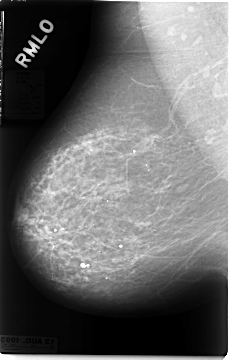

Volume: cancer_02 Case: C-0028-1

C_0028_1.RIGHT_MLO

RIGHT_MLO LINES 4672 PIXELS_PER_LINE 2976 BITS_PER_PIXEL 12 RESOLUTION 50 NON_OVERLAY